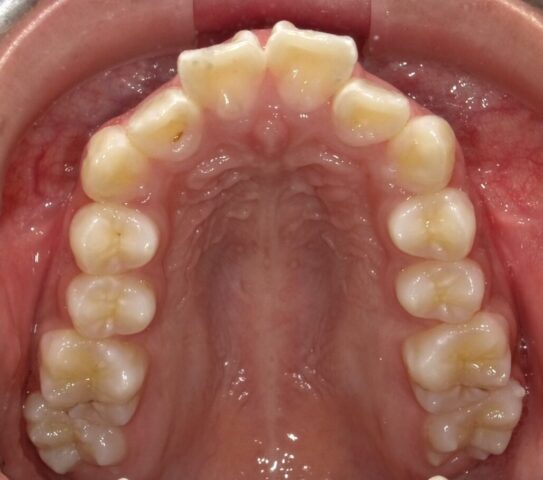

2024年6月(12歳8ヶ月)

永久歯揃いました。

本人のやる気がでたら

2段階目スタートします。